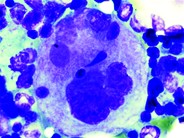

Blood smear showing proplatelet in the peripheral blood of a patient with myelodysplastic syndrome (arrow), May-Grünwald-Giemsa stain.